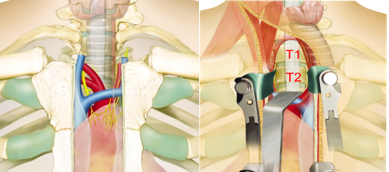

治疗策略及理由

治疗策略:行前路后纵韧带骨化块的切除,对脊髓进行减压。

理由:直接减压,避开手术的瘢痕。

术中照片或手术录像